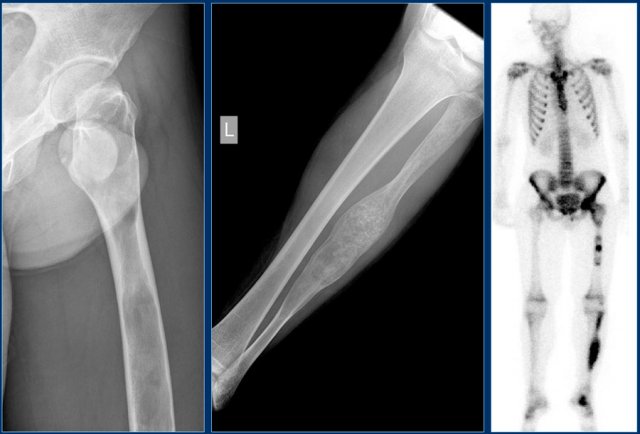

Ewing sarcoma (2)

On the left some examples of a Ewing sarcoma.

1. ill-defined lytic lesion of the femur diaphysis with a permeative pattern of destruction. Notice reactive sclerosis, irregular periosteal reaction and soft tissue mass.DD: ostesarcoma, lymphoma

2. Ewing sarcoma of the chest wall presenting with a large soft tissue mass. Many Ewing sarcomas are accompanied with a large soft tissue mass.

3. Ewing sarcoma of the proximal femur: almost normal radiographic appearance! See next images.

4. ill-defined lytic lesion in the distal humerus. Layered periosteal reaction laterally and irregular periosteal reaction with interruption on the antero-medial side.

5. Ewing sarcoma of the iliac bone. Hardly visible on plain radiograph. Continue with the discussion of this case.

Ewing sarcoma (3)

On the left images of a large lytic tumor arising from the right iliac bone.

On the plain film it is very hard to appreciate the lesion because of the permeative destruction pattern.

Scintigraphy shows extensive uptake within the iliac bone.

Sometimes, a cold spot is found in Ewing sarcoma.

MR reveals the intra- and extraosseous tumor extension.